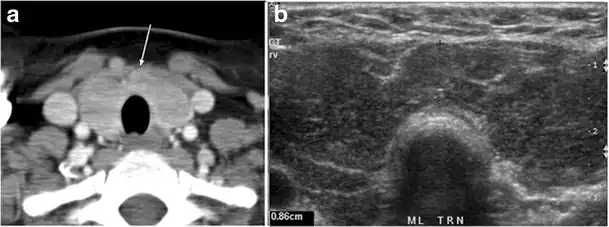

Fig. 9. A 58-year-old male patient with persistence PTC at thyroid bed with hypervascular nodal metastasis. a–c Transverse greyscale and colour Doppler neck ultrasound demonstrate hypoehoic soft tissue in the left thyroid bed (white arrow in a). There are a heterogeneous enlarged lymph nodes at level 2 and 3 with markedly increased vascularity (white arrow in b and c). d–f Enhanced axial CT images of the neck demonstrate a 2.7 × 1.4 cm hypodense soft tissue lesion anterior to the left carotid sheath (white arrow). There are left-sided enhancing abnormal and enlarged lymph nodes at cervical level 2 and 3 (black arrows).[1]

The likelihood of positive anatomic imaging is greater when serum Tg is >10 ng/mL. A diagnostic CT scan adds additional value to neck US in detecting central compartment macro-metastases in the mediastinum and retro-tracheal area. According to the recent American Thyroid Association guidelines, an upper chest and neck CT scan with IV contrast should be obtained when: 1) neck US is inadequate in visualizing possible local nodal disease (high Tg, negative neck US, and RAI imaging); 2) US is not able to delineate the disease completely, as in the case of bulky recurrent nodal disease; or 3) evaluation of possible recurrent invasive disease is needed (Figs. 7, 88 and and9).9). CT scans are also the most sensitive diagnostic tool for the detection of pulmonary micro-metastases. Many of the neck US features that are considered as suggestive signs of disease recurrence are also applicable to CT examination. These signs might include sizable rounded nodules in the thyroid bed, fine calcifications, or cystic change.[1]